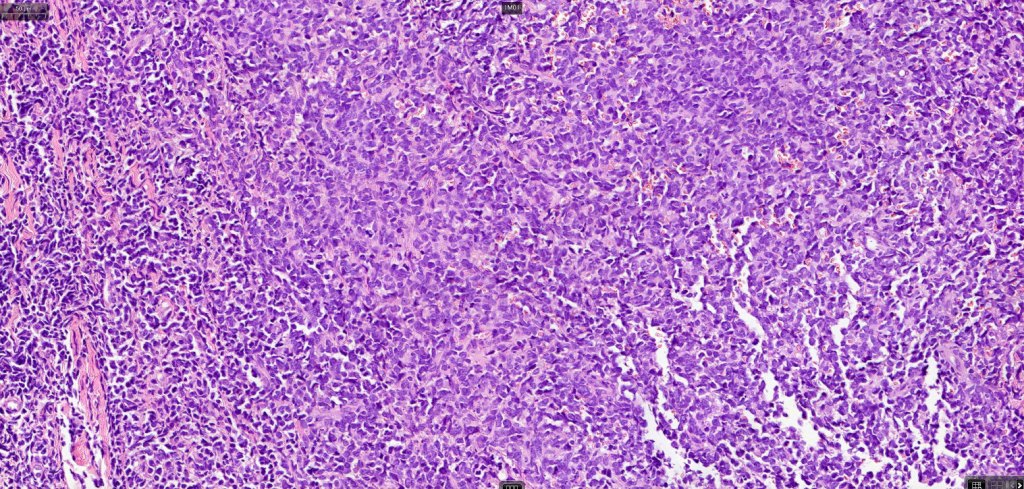

. Monotonous blast cells with gray-blue cytoplasm & irrregular vesicular nuclei with prominent nucleoli

. CD4, CD43, CD56, CD123, CD303, TCF4 & TCL1 +ve

. Variable CD68, CD7, CD33 & TdT +ve

. CD34, MNDA, lysozyme & myeloperoxidase -ve.

. Marked ki67 expression